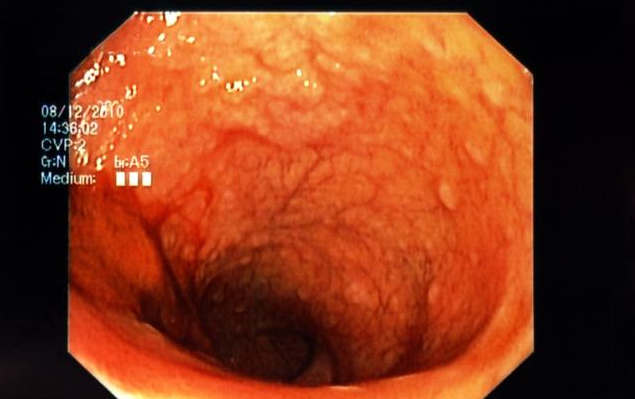

胃炎是各种原因引起的胃黏膜炎症,为最常见的消化系统疾病之一。按临床发病的缓急,一般可分为急性和慢性胃炎两大类型。